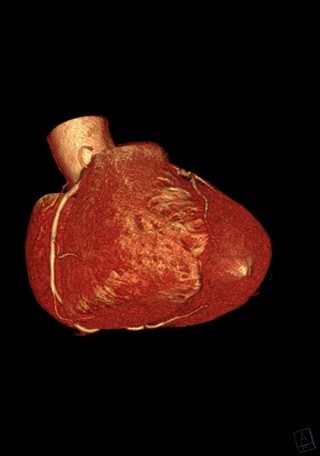

Artère interventriculaire gauche et artère circonflexe 3D